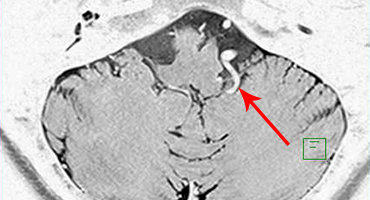

53歳女性、左舌咽神経痛

[画像所見]

-

頭部MRI -

頭部造影三次元CT

左後下小脳動脈が左舌咽神経を圧迫していたために左咽頭部を中心に激しい痛みが生じていました。